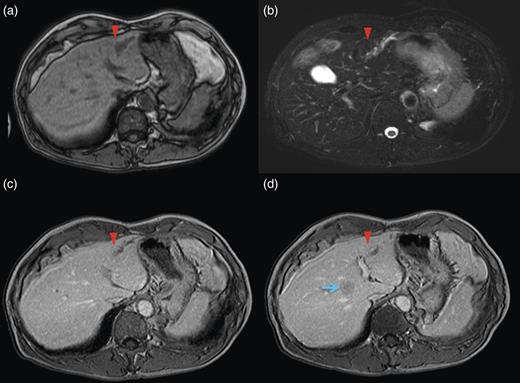

Magnetic resonance imaging (MRI) of the lateral segment lesion showed an irregular line shape lesion: hyper-intensity in T2-weighted; hypo-isointense in T1-weighted image (Fig. 2). These CT and MRI findings supported the identification of a fulfilment of tumour in B3. Endoscopic retrograde cholangiopancretography (ERCP) demonstrated a stricture involving the B2 and B3 hepatic ducts but not involving the left hepatic duct. Considering the patient's medical history along with the clinical features, the final diagnosis was secondary liver metastases due to primary descending colon adenocarcinoma, with the possibility of peripheral cholangiocarcinoma.